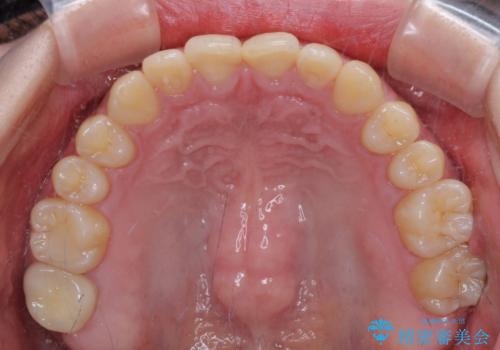

治療途中の奥歯と矯正治療の後戻り インビザライン・ライトによる矯正治療

- 根管治療を行ったままの奥歯と、矯正治療の後戻りを気にして来院された患者様です。

根管治療された歯に症状はなく、オールセラミッククラウンにて補綴治療を行うこととしました。

矯正治療の後戻りは軽微であったため、インビザラインの簡易パッケージであるインビザライン・ライトを用いて歯列を整えることとしました。

クラウンはよりよい咬み合わせで装着したいため、インビザラインを1セット使用して概ね歯列を整えた時点で補綴治療を行い、その後仕上げの矯正治療を行いました。